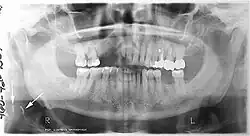

Panoramic radiograph

A dental panoramic radiograph, showing the maxilla and mandible, all the teeth including the "wisdom teeth," the frontal and maxillary sinuses, the nasal cavity and the temporomandibular joint and other near by head and neck anatomy.

A panoramic radiograph is a panoramic scanning dental X-ray of the upper and lower jaw. It shows a two-dimensional view of a half-circle from ear to ear. Panoramic radiography is a form of focal plane tomography; thus, images of multiple planes are taken to make up the composite panoramic image, where the maxilla and mandible are in the focal trough and the structures that are superficial and deep to the trough are blurred.